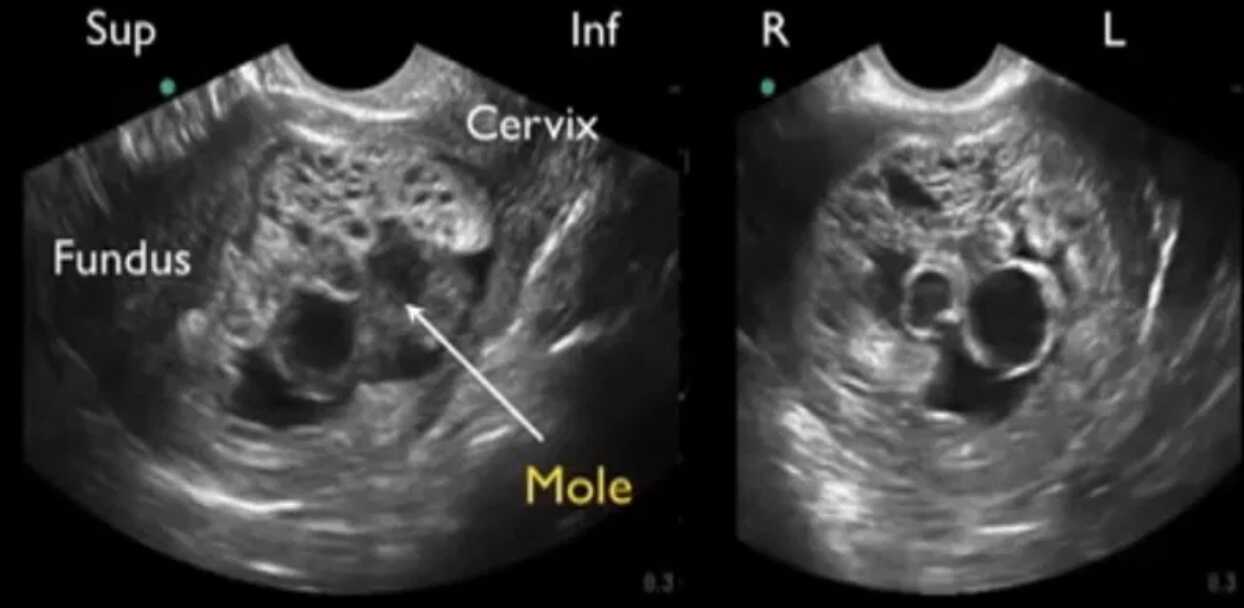

Gambar USG Hamil Anggur | Foto: TheAsianParent

Hamil anggur atau mola hidatidosa adalah kelainan kehamilan yang terjadi ketika sel telur yang telah dibuahi berkembang secara tidak normal.

Alih-alih membentuk janin dan plasenta sehat, sel-sel tersebut tumbuh menjadi kumpulan kista berisi cairan yang menyerupai buah anggur putih.

Pada pemeriksaan USG, dokter tidak menemukan detak jantung janin. Selain itu, ibu juga tidak merasakan gerakan janin sebagaimana mestinya, karena pada hamil anggur embrio biasanya tidak berkembang.

Pada USG, janin tidak terlihat di dalam rahim. Pada hamil anggur lengkap, memang tidak terbentuk janin sama sekali; jaringan yang tampak hanyalah pertumbuhan plasenta yang berubah menjadi gelembung-gelembung kecil.

Kantung ketuban tidak tampak atau tidak terbentuk sebagaimana mestinya. Hal ini berbeda dengan kehamilan normal, di mana sejak usia 5–6 minggu (USG transvaginal) biasanya sudah dapat dikenali kantung kehamilan dan menyusul kantung yolk/ketuban.

USG menunjukkan penebalan jaringan plasenta berisi banyak kista-kista kecil sehingga menimbulkan pola “badai salju” atau gelembung anggur. Gambaran inilah yang paling sering diacu masyarakat sebagai gambar hamil anggur.